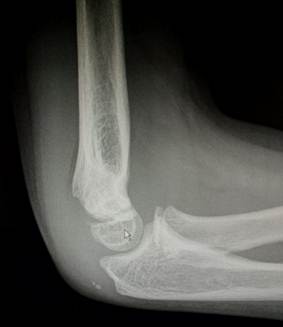

7 лет – 10 лет

В этом возрасте начинается процесс окостенения медиального вала

блока, в котором появляются мелкие, неправильной формы ядра окостенения. В 8

лет появляется ядро окостенения вершины локтевого отростка. Чуть позже к нему

добавляются мелкие ядра - спутники. К концу периода появляется ядро окостенения

латерального надмыщелка.

11- 13 лет

Это возраст, в котором все ядра окостенения достигли максимального

развития и приняли формы соответсвующих образований. На рентгенограммах их

разделяют узкие полоски ростковых зон. Это максимальный расцвет детского локтя.

Возраст

12 лет. Все ядра окостенения локтя развиты и разделены узкими хрящевыми

прослойками. Вершина локтевого отростка содержит основное ядро окостенения и

ядро – спутник неправильной формы.

14 лет. Стремительное закрытие зон роста локтевого сустава. Можно заметить

узкие просветы в основании медиального и латерального надмыщелков, а также пока

еще открытую зону роста в локтевом отростке.

Иногда

трудности с интерпретацией рентгенологической картины локтевого сустава

возникают даже у многоопытных специалистов. И что тогда делать? – Надо сделать

рентгенограммы противоположного, здорового сустава и сравнить. Но в большинстве

случаев внимательное изучение анамнеза, клинической картины и рентгенограммы

позволяет принять правильное решение и без этого.